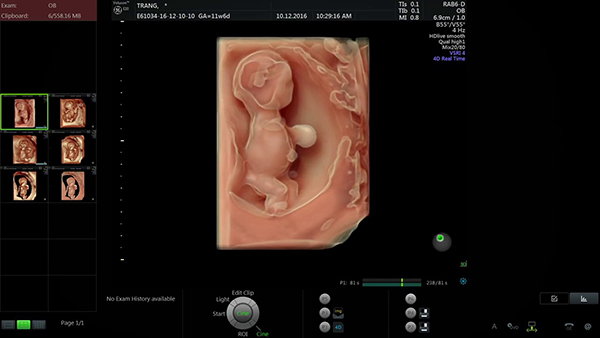

Hình ảnh Siêu âm thai 11 tuần 6 ngày

Siêu âm thai 11 tuần 6 ngày có thể dự đoán dị tật bẩm sinh